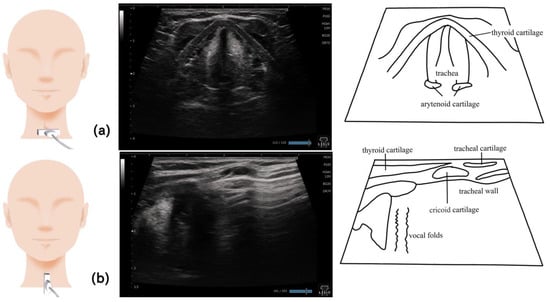

12. Esophagus (Figure 12)

13. Larynx (Figure 13)